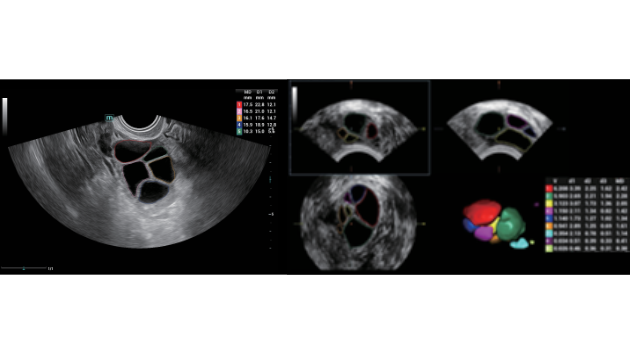

Ongeacht of u werkzaam bent in een ziekenhuis of kliniek, of uw vaardigheden aanscherpt op het gebied van algemene beeldvormingstoepassingen, vrouwengeneeskunde of cardiovasculaire specialismen, in deze serie vindt u zeer krachtige hulpmiddelen waarmee u aan kop kunt blijven.